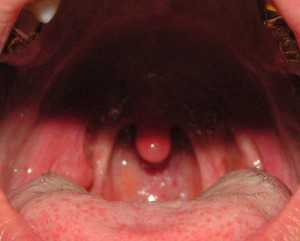

Воспаление в гландах (тонзиллит) не может остаться незамеченным, ведь данная проблема сопровождается характерными симптомами. Одно из основных проявлений недуга — визуальные изменения тканей глотки, а в частности самих миндалин. Гланды здорового человека имеют размеры миндального ореха, а с присоединением воспаления значительно увеличиваются в размерах. Также отмечается сильное покраснение глотки, появление налёта и спаек на границе с дужками нёба.

Признаки заболевания проявляются не только физическим состоянием пациента, но и внешне. При осмотре пациента отоларингологом он замечает, что миндалины поменяли свой цвет. Если у пациента наблюдается воспалительный процесс, то гланды становятся ярко красного цвета. Также доктор замечает значительное увеличение миндалин в размерах. По своим размерам они напоминают не зерна миндаля, а грецкие орехи. Для миндалин характерна рыхлость. У большинства пациентов возникают спайки рубцового характера между гландами и дужками неба.